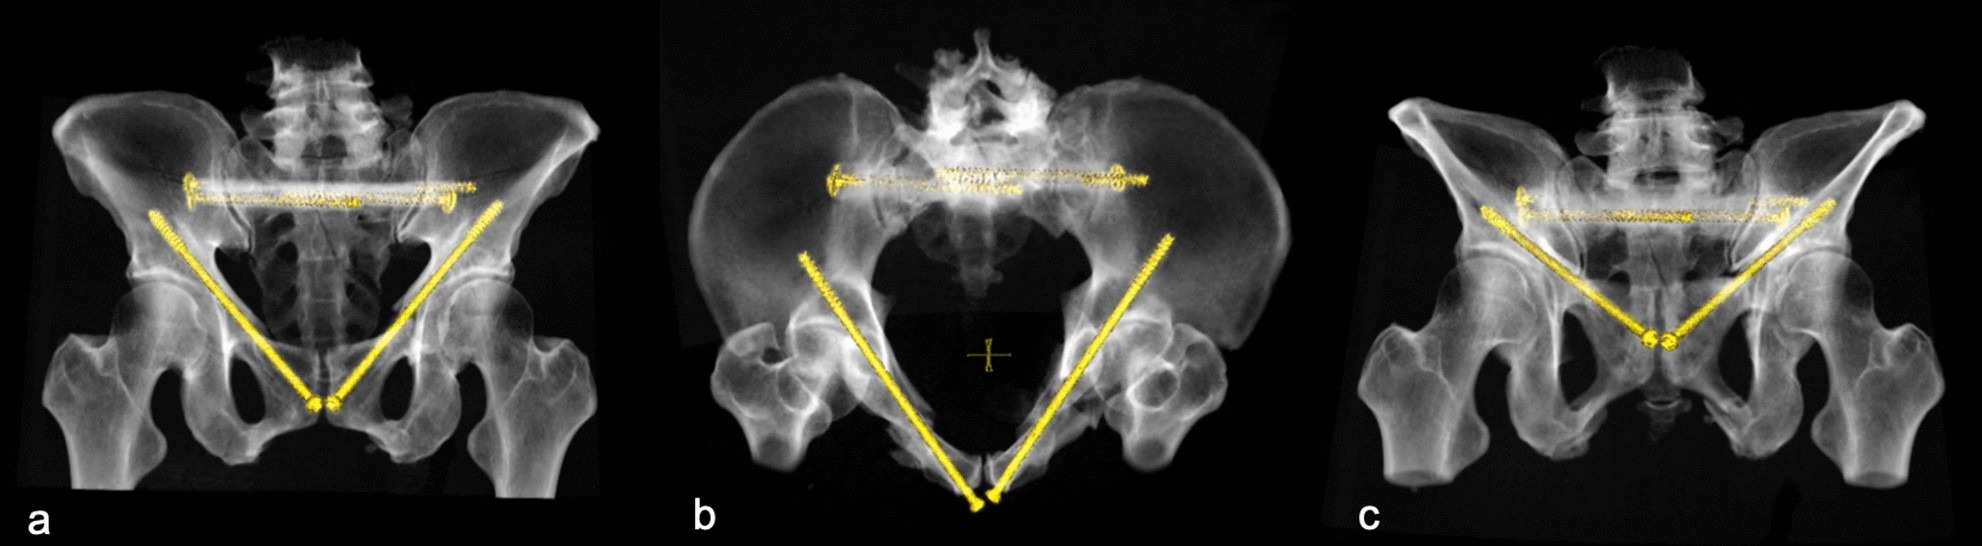

Figure 1

Bilateral retrograde transpubic screw fixation in a patient pelvic ring fracture after traffic accident (a) ap view (b) inlet view (c) outlet view. This figure was generated using the software Sectra PACS (Version 22.1, Linköping, Sweden; www.medical.sectra.com).